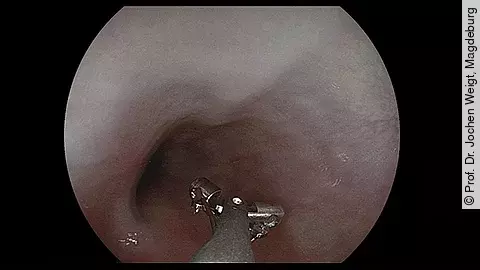

Endoskopisches LehrvideoAortoduodenale Fistel

In unserem neuesten Video sehen Sie einen kurzen Ausschnitt aus einer Endoskopie, die Prof. Dr. Jochen Weigt aus Magdeburg im Auftrag seine gefäßchirurgischen Kolleginnen und Kollegen durchführte, um nach einer eventuell vorliegenden aortoduodenalen Fistel zu suchen.